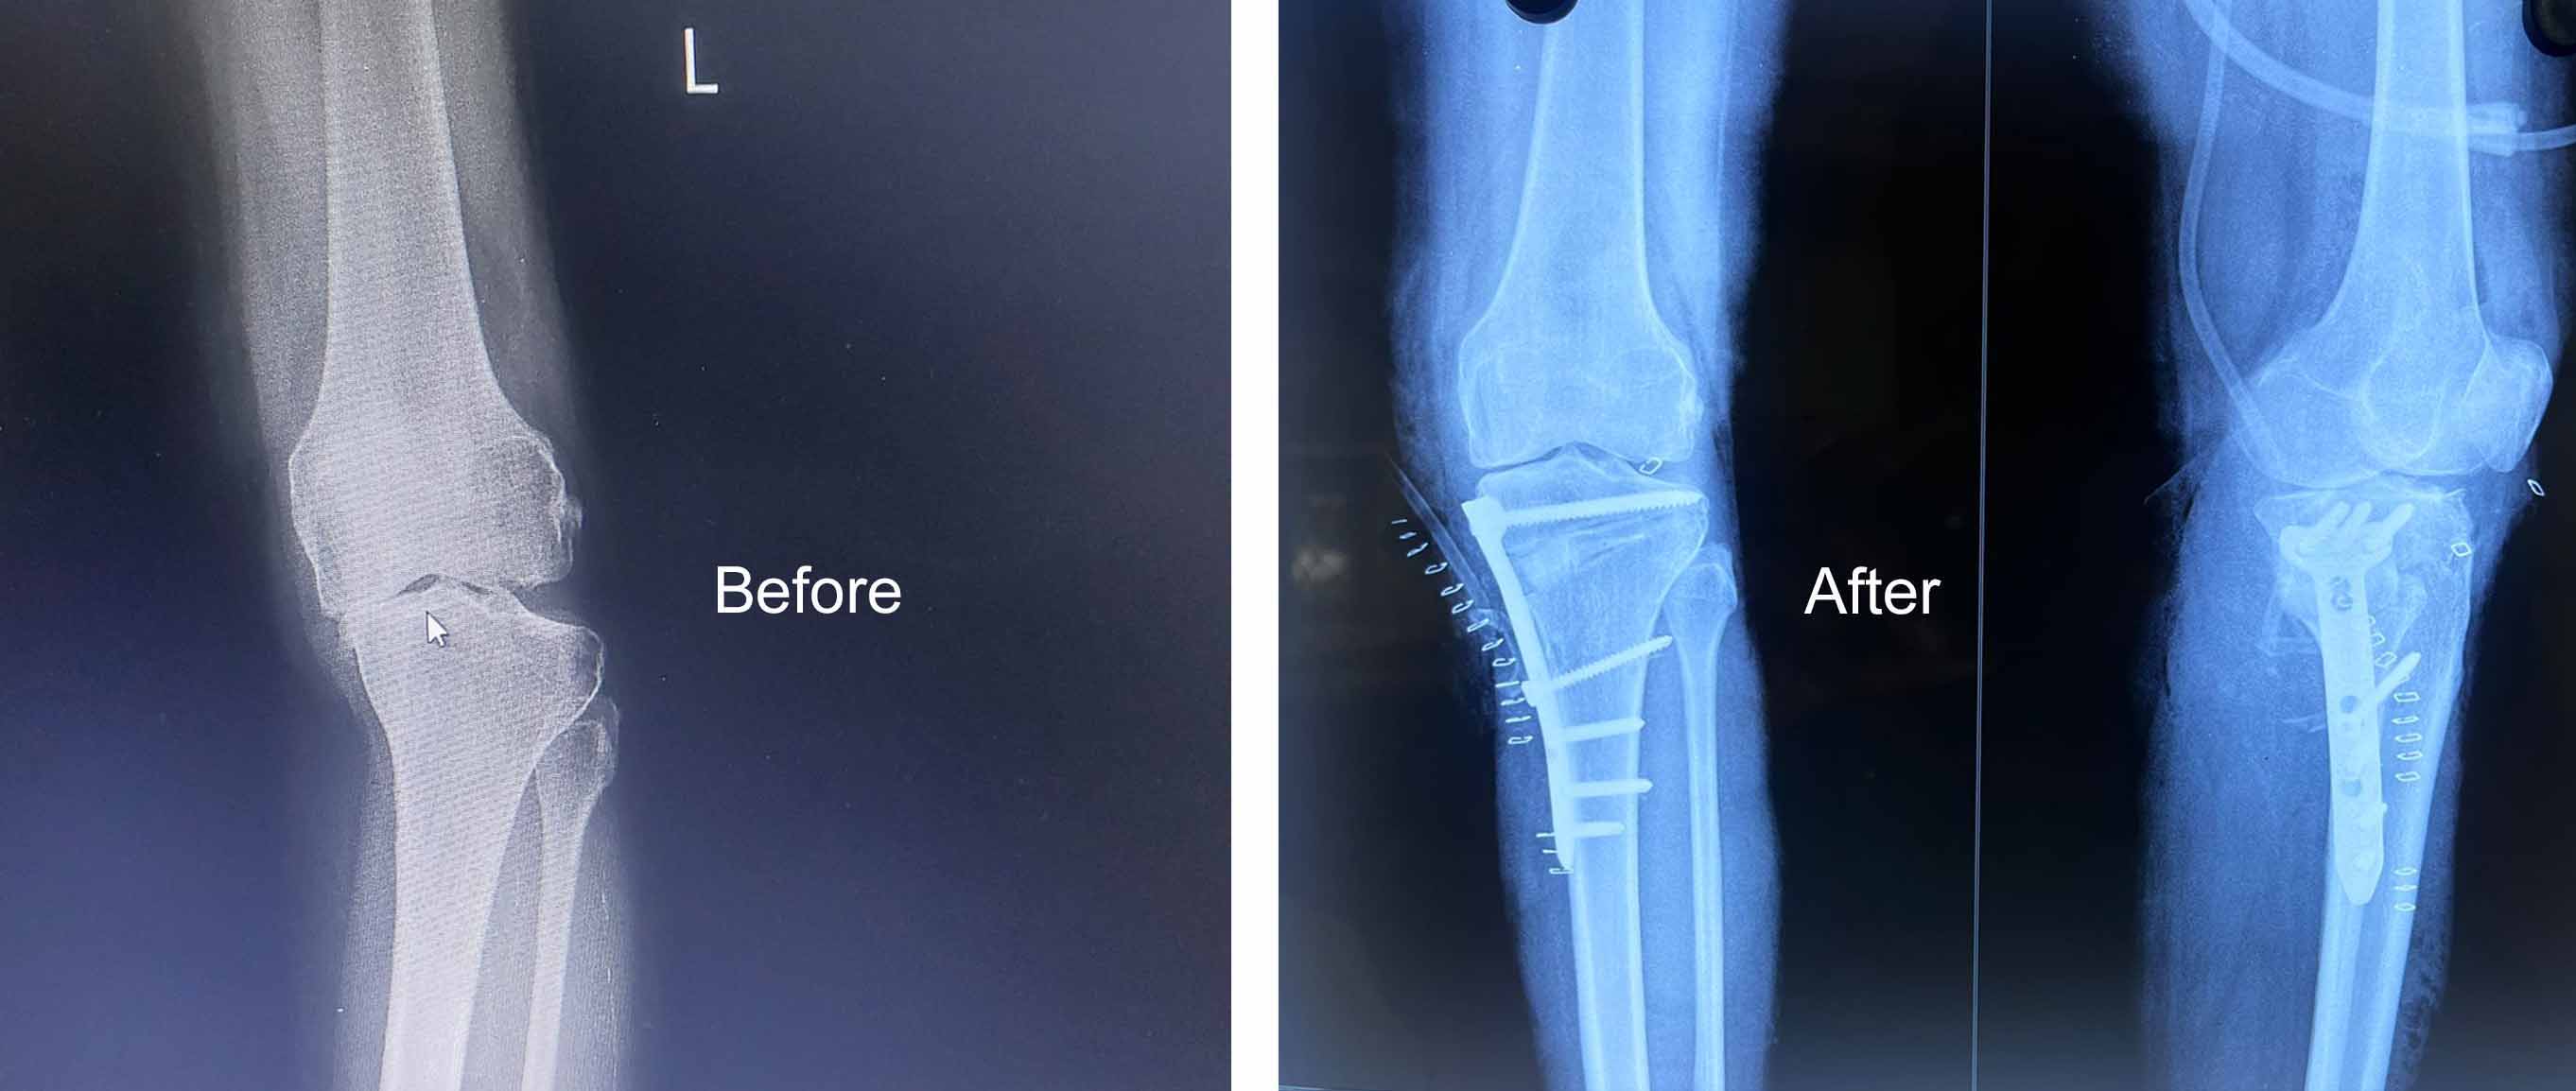

Dr Muhammed Riyadh is a distinguished medical professional in the field of orthopedics, has made significant contributions to the healthcare industry through a career marked by expertise, compassion, and unwavering dedication to patient well-being

Gallery